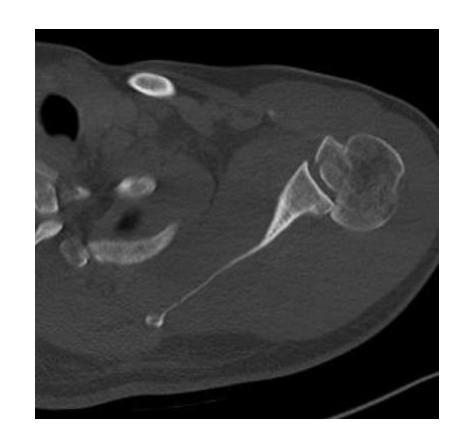

Osteochondroma

What is the diagnosis?

- X-ray showing bony tumor growing away from the epiphysis

- Diagnosis: Osteochondroma

Clinical Features:

- Pain since 2 years in proximal humerus

- Malignant transformation is rare (<1%)

- Treatment: Monitor with ESR, follow-up every 6 months-1 year

- Surgery considered if severe pain (suggesting malignant transformation)

- Surgical risk: Drop hand due to radial nerve injury